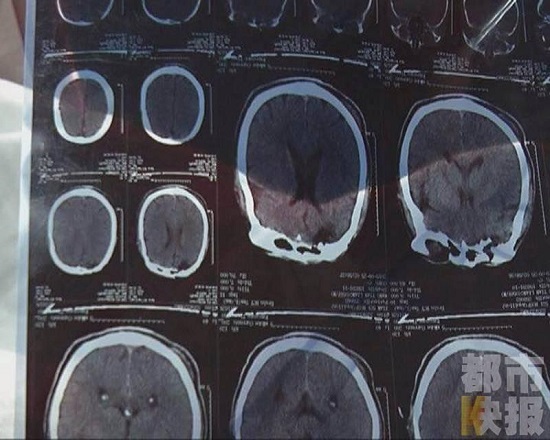

老公把手搭在老婆肩上,單單是因?yàn)檫@個(gè)就打了人?這原因?qū)嵲谑亲屓艘馔狻6矣浾咦⒁獾?,劉大姐的臉上也有淤青。王師傅本身有殘疾,醫(yī)生說他的頭部可能受傷,但是還需要繼續(xù)檢查,現(xiàn)在仍然在醫(yī)院里接受治療。而打人男子已經(jīng)被帶至轄區(qū)派出所接受民警的進(jìn)一步調(diào)查。